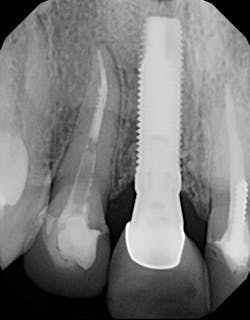

No. 4: Poor bone-to-implant contact (BIC)

Although an implant may seem to be surrounded by bone on a two-dimensional and even a three-dimensional radiograph and CT scan, that bone may be of poor quality and/or not completely intimate with the implant surface (figure 4).

Poor BIC can occur when fibrous tissue encapsulates the body of the implant, which is then layered with bone. Radiographically the implant appears as if the bone levels are normal, and clinically the implant may exhibit no signs of mobility; however, the patient still experiences dental pain. This can be evident especially when the implant is put into function with a healing abutment or loaded with a crown. A possible solution to detect poor BIC is the use of a

resonance frequency analysis machine that will give a digital reading of the strength of the implant-bone connection.